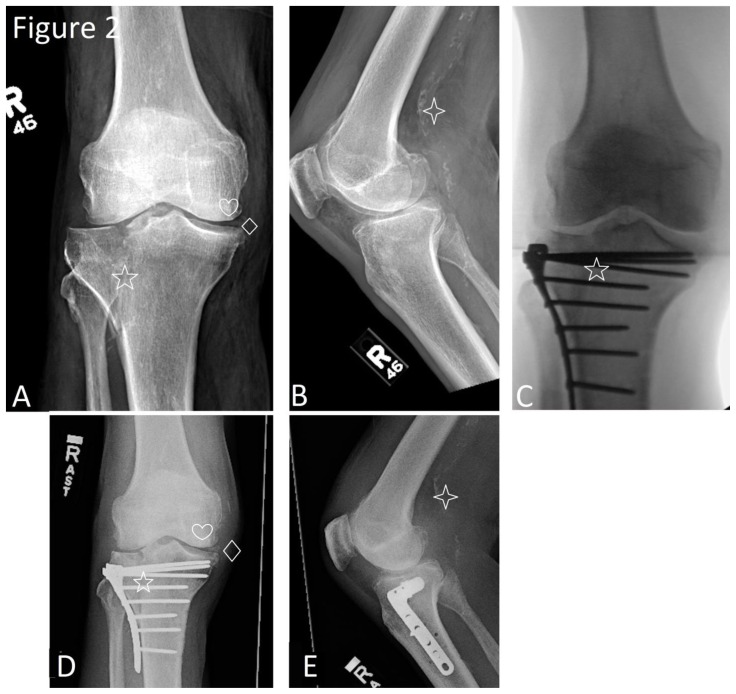

Figure 2.

82-year-old male with a comminuted Schatzker II fracture of the lateral right tibial plateau with depression and incidentally discovered calcification of the anterior cruciate ligament.

Findings: Antero-posterior and lateral radiographs of the right knee. A.) Preoperative antero-posterior radiograph demonstrating the tibial plateau fracture (star symbol), degenerative changes of the medial compartment (heart symbol) and chondrocalcinosis of the medial meniscus (diamond symbol). Of note, calcification of the anterior cruciate ligament is not visualized. B.) Preoperative lateral radiograph demonstrating atherosclerosis (four pointed star symbol). Again, calcification of the anterior cruciate ligament is not visualized. C.) Intraoperative antero-posterior radiograph demonstrating tibial plateau fracture (star symbol) adjacent origin of anterior cruciate ligament with poorly visualized ligament and calcification. D.) Antero-posterior and E.) lateral radiographs of the right knee following the fixation of the fracture with plate and screws demonstrate the tibial plateau fracture in near anatomic alignment with hardware in place as denoted by the star symbol. Degenerative changes of the medial compartment (heart symbol), chondrocalcinosis of the medial meniscus (diamond symbol) and atherosclerosis (four pointed star symbol) remain unchanged. Of note, in this view, the anterior cruciate ligament is still poorly visualized and calcification within the region cannot be confirmed.

Antero-posterior and lateral radiographs of the right knee following the procedure demonstrated the tibial plateau fracture in near anatomic alignment with hardware in place (figure 2).

In our study, antero-posterior and lateral radiographs of the right knee demonstrated the tibial plateau fracture but failed to show the anterior cruciate ligament calcification (figure 2). A subsequent CT of the lower extremity revealed a comminuted fracture of the lateral right tibial plateau with depression, chondrocalcinosis, severe degenerative disease and the calcification of the anterior cruciate ligament (figure 1).